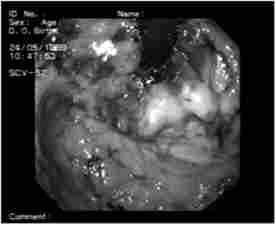

Тільки виконання такого завдання дозволить поліпшити результати лікування онкологічних хворих. Для цього застосовують різні барвники, що дозволяють більш чітко виділити зону ураження (рис. 5.4), і яка збільшить ендоскопію (ZOOM-ендоскопія) (рис. 5.5).

Мал. 5.4. Ендофото.

Забарвлення слизової оболонки, ураженої пухлиною